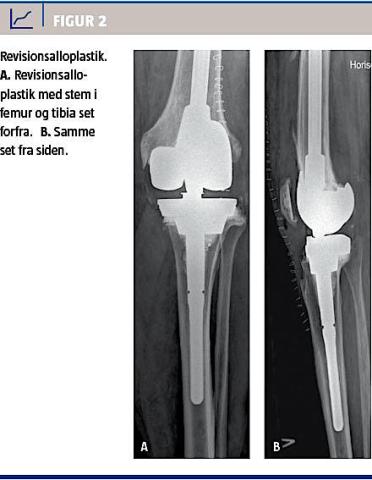

Osteotomi

Osteotomi kan udføres ved let til moderat artrose isoleret til det mediale eller laterale kammer. Behandlingen tilsigter at flytte belastningen til det ikkeafficerede ledkammer, hvorved patientens symptomer bedres. Figur 1 viser et tilfælde af isoleret medial

etkammerartrose, der er behandlet med proksimal

tibiaosteotomi.